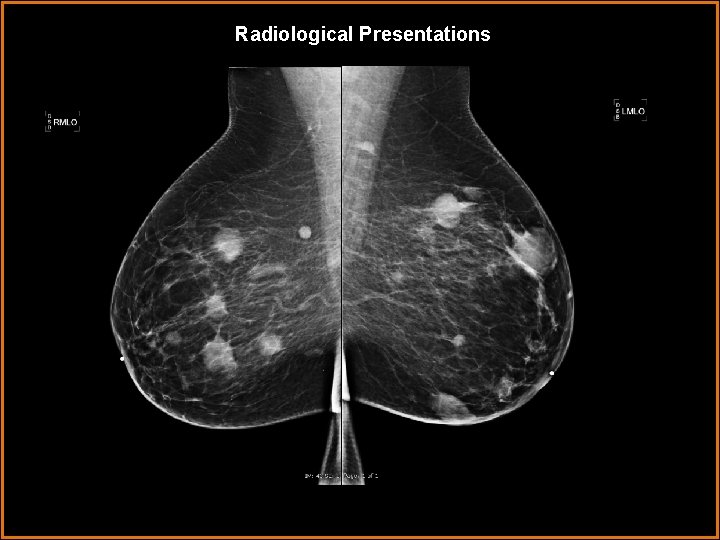

Radiological Presentations

Findings and Differentials Findings: The mammogram demonstrates multiple masses within the breasts, bilaterally. Differentials: • Primary breast cancer with metastatic disease. • Multifocal breast cancer versus synchronous breast cancer. • Cutaneous lymphoma. • Multiple cysts • Multiple fibroadenoma